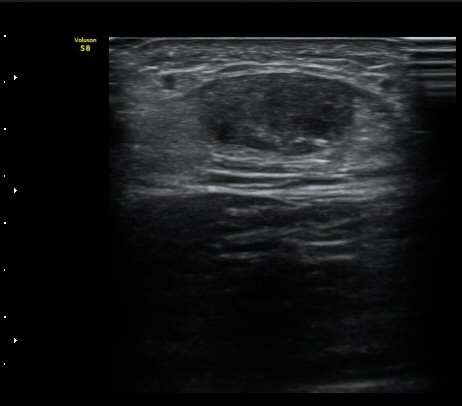

ÃÊÀ½ÆÄ °Ë»ç

d